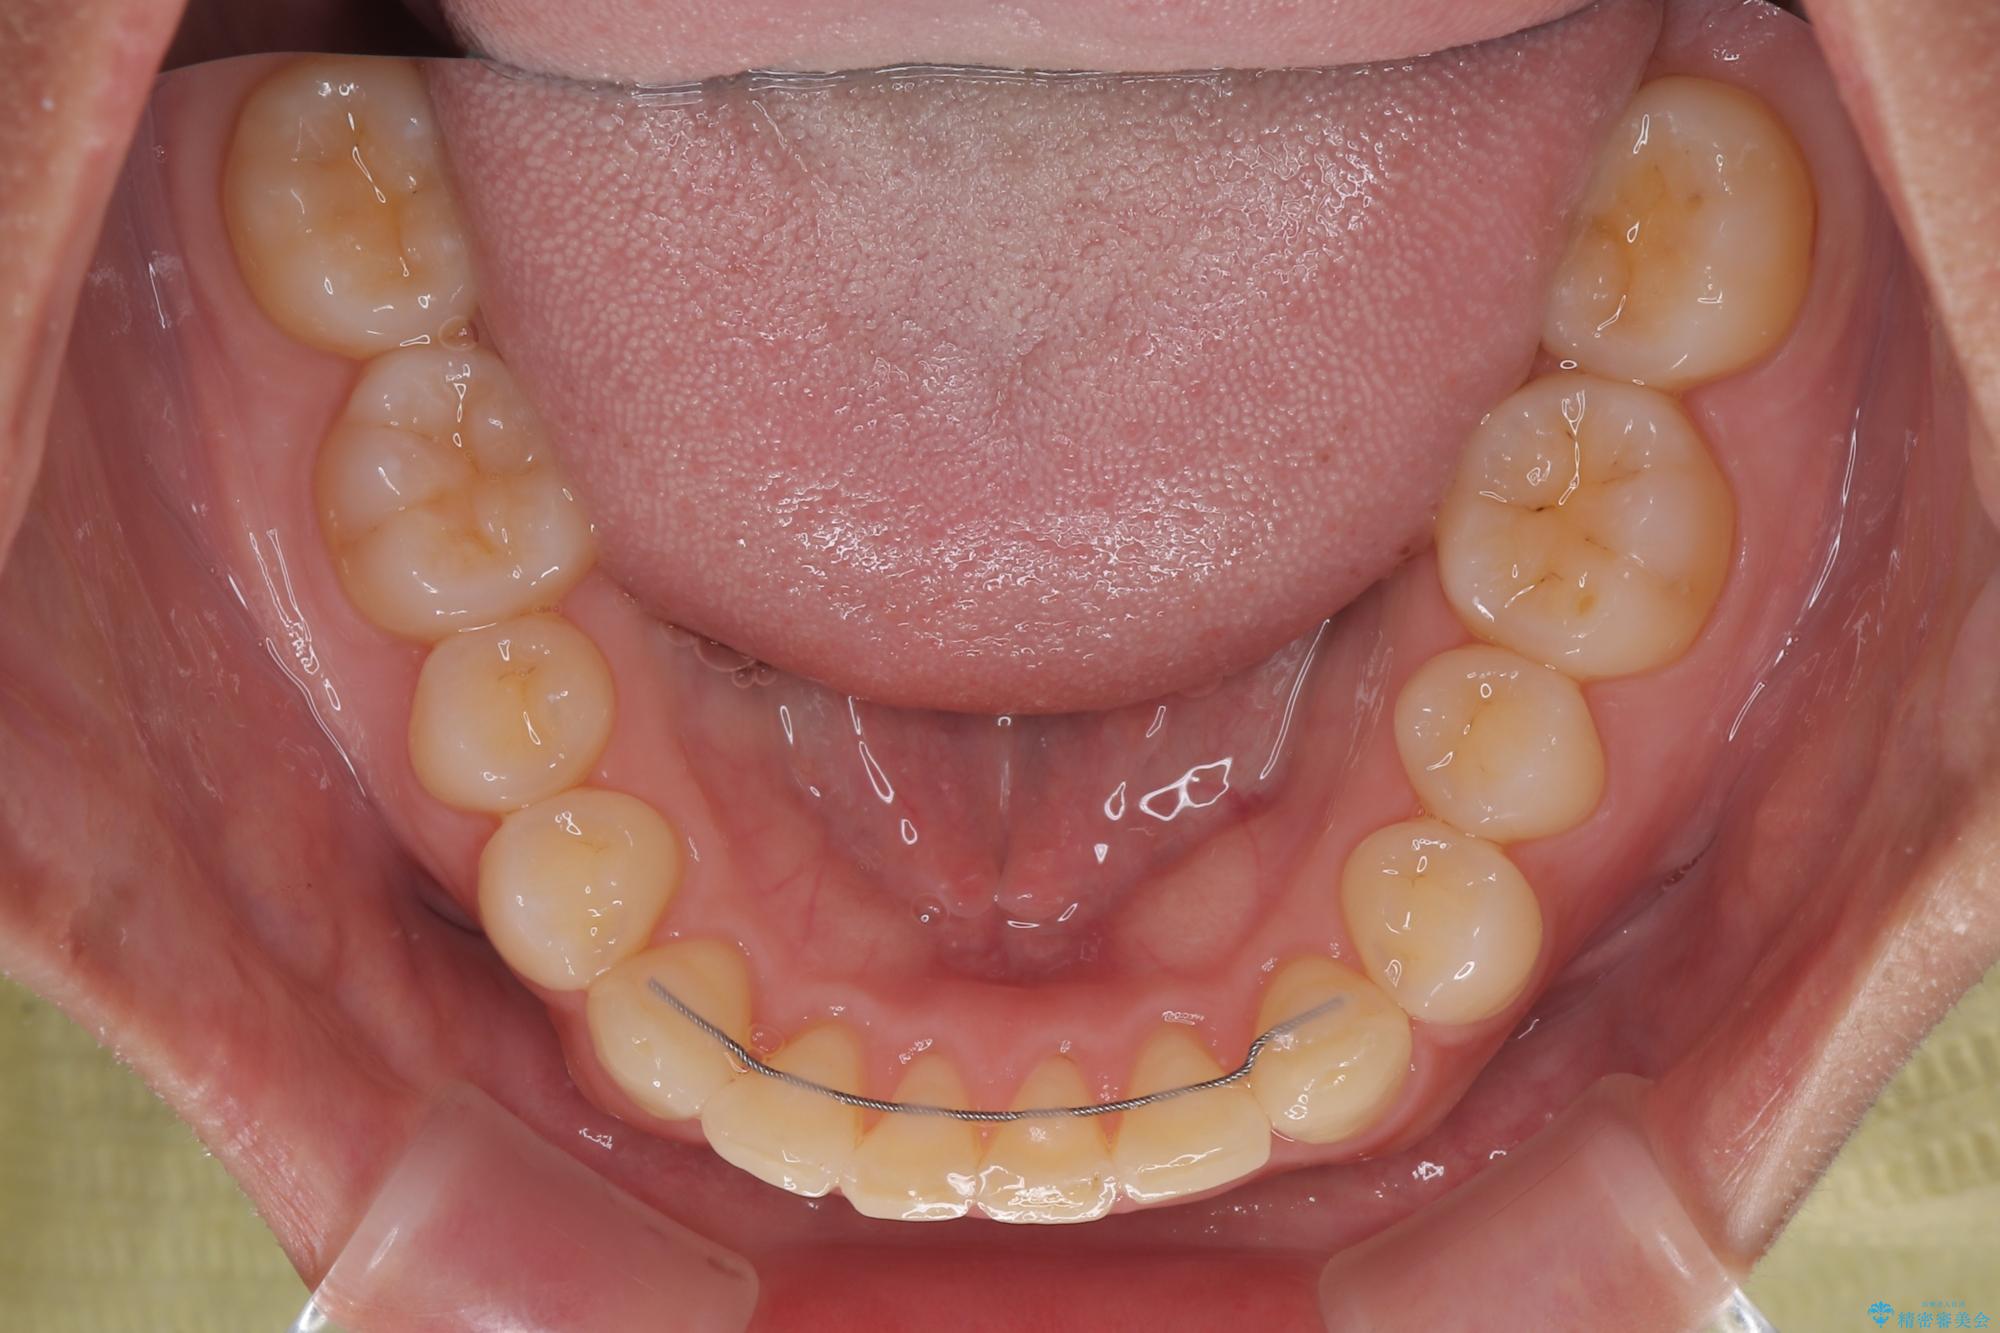

隠れた前歯が気になる ディープバイトのワイヤー矯正治療

- 下顎前歯が完全に隠れてしまっていることを気にして来院された患者様です。

下顎の臼歯が手前に傾斜していることで咬み合わせが深くなってしまい、下顎前歯が見えないほどに上顎前歯が覆い被さっている状態でした。

下顎臼歯を起き上がらせるためにユーティリティーアーチを使用し、一気に深い咬み合わせを改善することができました。